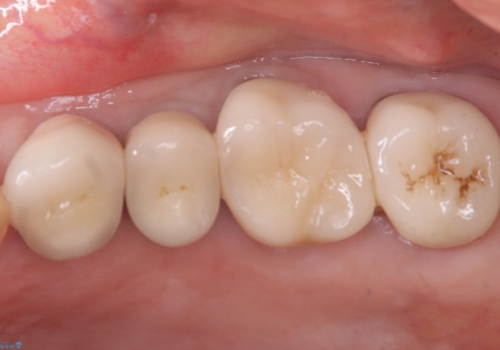

- 主訴:昔入れた被せものの境目の黒いところが気になる

クラウンの不適により境目に汚れが溜まり、黒く見えていました。

適合の良いクラウンへやり替えることとしました。